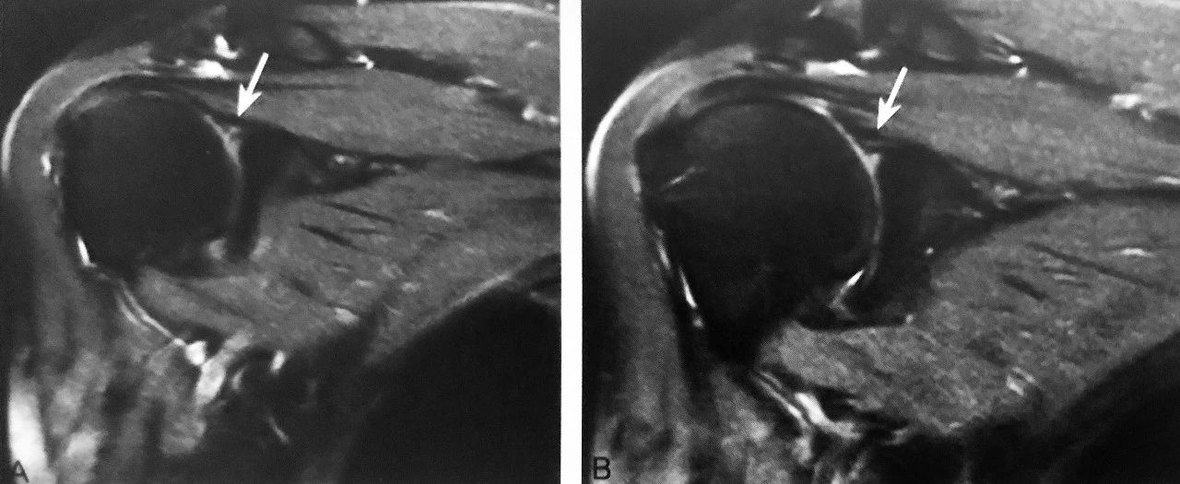

A、B 图为同一患者, 压脂 T2WI 示右肩关节腋囊少许积液,右盂肱下韧带肱骨附着处部分撕裂并回缩,形成 J 征

判读要点:

1、肱骨附着处撕脱的直接征象;

2、在肩关节 MRI 斜冠状位压脂 T2WI 或 MRI 造影上观察;

3、右肩 HAGL 损伤表现为 J 征,左肩 HAGL 损伤表现为反 J 征。